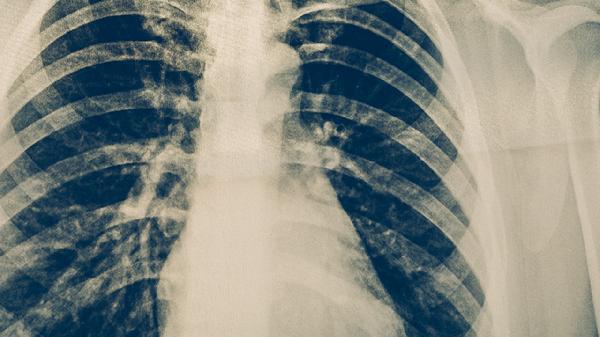

肺膿腫患者可出現(xiàn)高熱、咳大量膿臭痰,X線顯示空洞伴液平面,需與肺結核空洞鑒別。肺膿腫多由厭氧菌感染引起,起病急驟,血培養(yǎng)可能陽性。肺結核空洞痰液無臭味,病程遷延。臨床常用甲硝唑氯化鈉注射液、注射用哌拉西林鈉他唑巴坦鈉、鹽酸莫西沙星片等藥物治療肺膿腫。